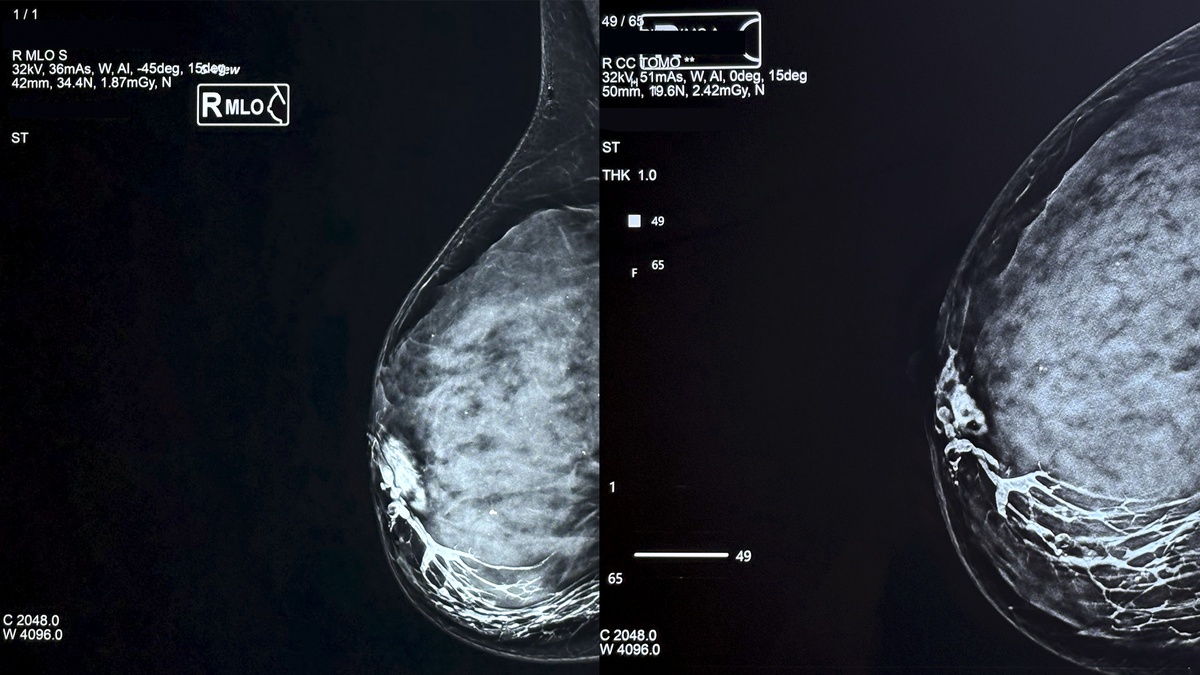

"ампутация" протока в нижне-наружном квадранте правой молочной железы патологическим образованием